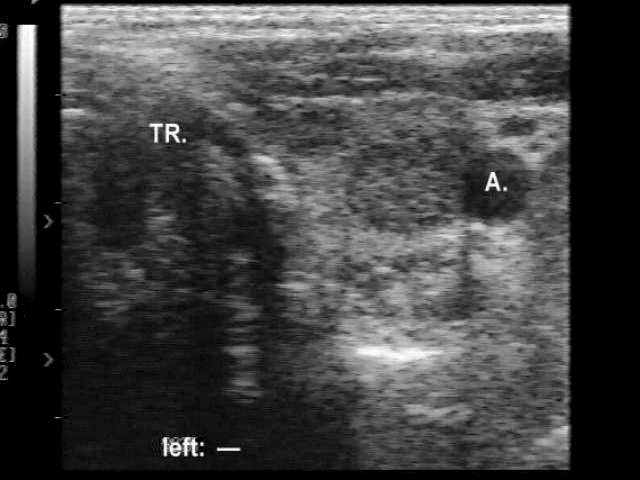

Ultrasonography. Besides the enlarged lymph nodes, US revealed a hypoechogenic lesion in the left lobe of the thyroid.